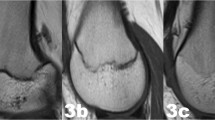

The examinations of the volunteers were sorted separately for both sexes from youngest to oldest. In a first step, all slices of each examination were then looked through to get an overview of the general morphology of the growth plate and the process of its ossification. This was done without knowledge of the exact age of the volunteers. In a second step, sketches of the found characteristics and changes of the growth plate were drawn for both sequences. Here, the separation by sex was dropped since unlike the chronology of the ossification the morphology of the growth plate showed no sex-related differences. Only characteristics that could be found alike in most cases of similar age were taken into account. At this point a distinct continuum of the growth plate’s development could be recognised. The sketches were then sifted for easily identifiable changes, i.e. the presence or absence of certain features. These morphological features were then put into an ascending order and the following staging system was formulated as a hypothesis (see Figs. 1 and 2 for the corresponding schematics and examples; see Table 2 for the shortened version):

Schematic drawings for the stages of the T2 TSE SPIR sequence and examples (3.0 T; non-contrast enhanced; coronal slice orientation); from left to right: male 13 years, male 14 years, female 16 years, male 20 years, female 22 years. MRI magnetic resonance imaging; TSE turbo spin echo; SPIR signal pre-saturation with inversion recovery

Stage 2: In the T1-w sequence a continuous band of intermediate signal intensity is visible, walled by serrated lines of low to no signal intensity towards the epiphysis and the diaphysis.

In the T2-w sequence the epiphysis is demarcated by a serrated line of low to no signal intensity. The metaphysis shows two serrated lines of high signal intensity. Both lines can be continuous or discontinuous.

Stage 3: In the T1-w sequence a discontinuous band of intermediate signal intensity is visible. The band is walled by serrated lines of low to no signal intensity towards the epiphysis and the diaphysis that sporadically convene and interrupt the band, forming a single serrated line with no signal intensity.

In the T2-w sequence the metaphysis shows two serrated lines of high signal intensity that sporadically convene, forming a single thin and serrated line of high signal intensity.

Stage 4: In the T1-w sequence a discontinuous thin and serrated line of intermediate signal intensity between the epiphysis and the diaphysis is visible. In the continuity of the line, thicker sections with no signal intensity can be seen.

In the T2-w sequence a thin single, discontinuous or dotted line of hyperintense signal is visible in the same position as the described thin line of the corresponding T1-w sequence. In the continuity of the line, thicker hyperintense sections can be seen.

Stage 5: In the T1-w sequence a continuous thin line of intermediate signal intensity between the epiphysis and the diaphysis is visible.

The T2-w sequence shows a single thin, discontinuous or dotted line of hyperintense signal in the same position as the described thin line of the corresponding T1-w sequence.

Stage 6: In the T1-w sequence a continuous thin line of intermediate signal intensity between the epiphysis and the diaphysis is visible.

The T2-w sequence shows no hyperintense signal in the same position as the described thin line of the corresponding T1-w sequence.

The stages are based on the presence or absence of certain landmarks of the epiphyseal-diaphyseal fusion’s morphological appearance, mainly drawn from the T1-w sequence. In the T1-w sequence they are characterised by the presence of a continuous band-like morphology of the growth plate (stage 2), the presence of a discontinuous band-like morphology (stage 3), the beginning thin-lined demarcation of the fusion’s “scar” (stage 4), the completely demarcated fusion’s “scar” with a corresponding T2-hyperintense signal (stage 5) and finally without a corresponding T2-hyperintense signal (stage 6). Stages 5 and 6 have the exact same appearance in the T1-w sequence and cannot be further differentiated without the T2-w sequence.